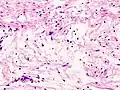

Micrograph of a schwannoma showing both a cellular Antoni A area (top) and a loose paucicellular Antoni B area (bottom). HE stain.

Verocay bodies are seen histologically in schwannomas.